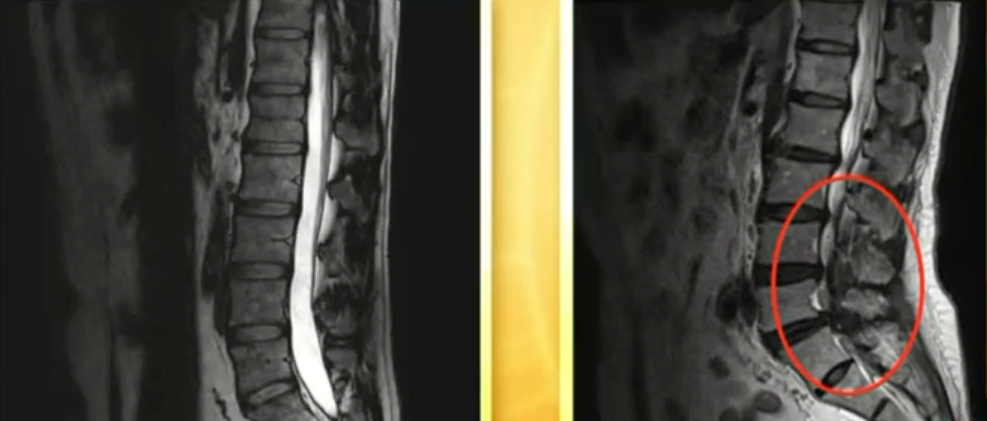

腰椎间盘突出复位了:“北上广大医院都跑遍了,也没治好我的多年腰突,愁的整天睡不着觉!用了这个铁板腰贴,奇迹般复位了,腰不疼了,腿也不麻了!”